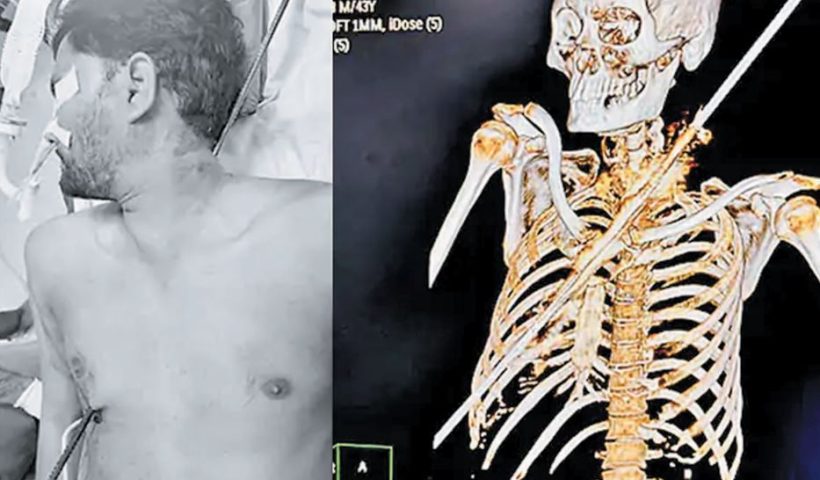

View More મતિભ્રષ્ટ કારચાલકે ગંભીર દર્દીને લઈ જતી 108ને 38 મિનિટ સુધી સાઈડ ન આપીયુવાનનું ગળું વીંધી સળિયો છાતીમાંથી નીકળ્યો

સુરતમાં રસ્તે ચાલીને જતા યુવાન ઉપર ઓચિંતી આફત ત્રાટકી, સર્જરી કરી જીવ બચાવતા તબીબો સુરતના ઉત્રાણમાં સંગતમ નામની બની રહેલી બિલ્ડિંગ પરથી 10 ફૂટનો સળિયા…